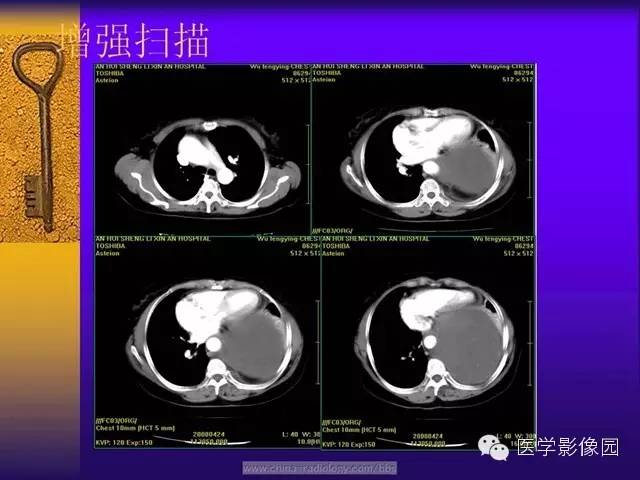

增强扫描,动脉期肿瘤的周边强化明显并见多支供血动脉显影的“地图样”强化,静脉期瘤体呈现明显不均匀强化,这与肿瘤内的细胞密集区富有薄壁的“鹿角状”分支血管密切相关。肿瘤的血管丰富区、细胞密集区强化明显,强化早期肿瘤的供血血管从肿瘤的边缘向肿瘤内部沿伸,因此,强化早期瘤内迂曲血管影显示清晰;细胞稀疏区、胶原纤维密集区、黏液变性强化相对较弱,呈现静脉期强化,坏死囊变区始终未见强化。由于SFT的病理学表现多样,因此其增强后可出现多种强化形式,动脉期肿瘤内可见迂曲的供血血管由肿瘤边缘向肿瘤内部延伸,静脉期进行性强化对于诊断及鉴别诊断具有重要意义。